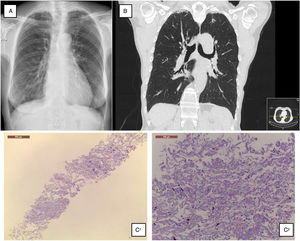

A 68-year-old Caucasian woman was referred to ILD outpatient clinic with recurrent episodes of a dry cough for the past two years, significantly worsened in the last six months, and consolidations in both upper lobes in thoracic high-resolution computed tomography (HRCT) scan. She had atrial fibrillation diagnosed five years before, under amiodarone and warfarin since that time. Additionally, nimodipine was also prescribed due to arterial hypertension since its diagnosis. Physical examination did not show any relevant remarks, namely in the thoracic evaluation. Besides the values in the normal range concerning hemogram, hepatic and renal function, the serum autoimmune panel was negative. Any microorganism was found in the sputum. Lung function tests showed normal lung volumes (forced vital capacity • 144.5%, forced expiratory volume in the 1° second • 129.4%, total lung capacity • 119%) and diffusion capacity of carbon monoxide of 79.3%. Additionally, arterial blood gases had values into the normal range, and in six-minute walk test, the patient walked 452m, without significant oxygen desaturation (minimum oxygen saturation 95%). Chest radiograph showed subpleural thickening at upper lobes (Fig. 1A), predominantly in the right hemithorax; these findings were more evident in the chest HRCT scan, associated with parenchymal reticulation and peripheral traction bronchiectasis at upper lobes, with no abnormalities at lower lobes (Fig. 1B). Chest radiographs performed previously and during the amiodarone prescription did not show any relevant features. The histology obtained by computed tomography-guided transthoracic biopsy in the left lung apex showed fibrosis, with dense collagen and elastic fibres, compatible with PPFE. (Fig. 1C) After discussion in a multidisciplinary meeting, since clinical, imaging and histology all were compatible with PPFE, this diagnosis was established. After a careful evaluation did not found any of the potential causes previously described added to the fact that one of the most frequent amiodarone side effects is lung toxicity, with a multiplicity of patterns, amiodarone was then considered as a potential cause.

(A) Chest radiograph shows bilateral apical subpleural thickening; (B) coronal CT imaging shows subpleural thickening and reticular opacities with traction bronchiectasis in the parenchyma at the upper lobes, more predominant in the right side; (C) 1 • low magnification showing fibroelastotic scarring; 2 • at high magnification the typical mixture of fragmented elastic fibres and collagen.